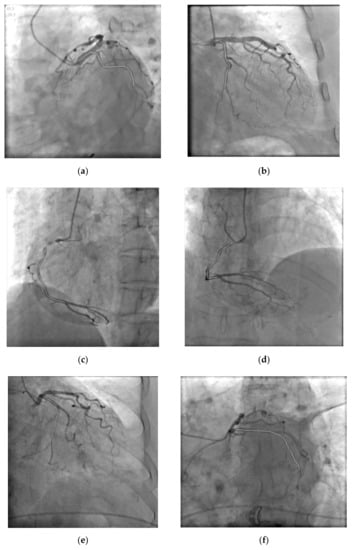

Figure 9 is the process of constructing the CBOCD. Where there is overlap or parallel to the contrast line, it is correctly marked as shown in Figure 9a. The convex arcs on the blood vessels are also detected correctly by using the method proposed in this paper, as shown in Figure 9b. The low brightness segments were also correctly marked as shown in Figure 9c. However, it still has some false recognition due to the influence of background brightness, as mentioned above.

Figure 9.

The CBODE of Data 1. (a) is the Brightness OPE; (b) is the Curvature OPE; (c) is the content of CBODE.